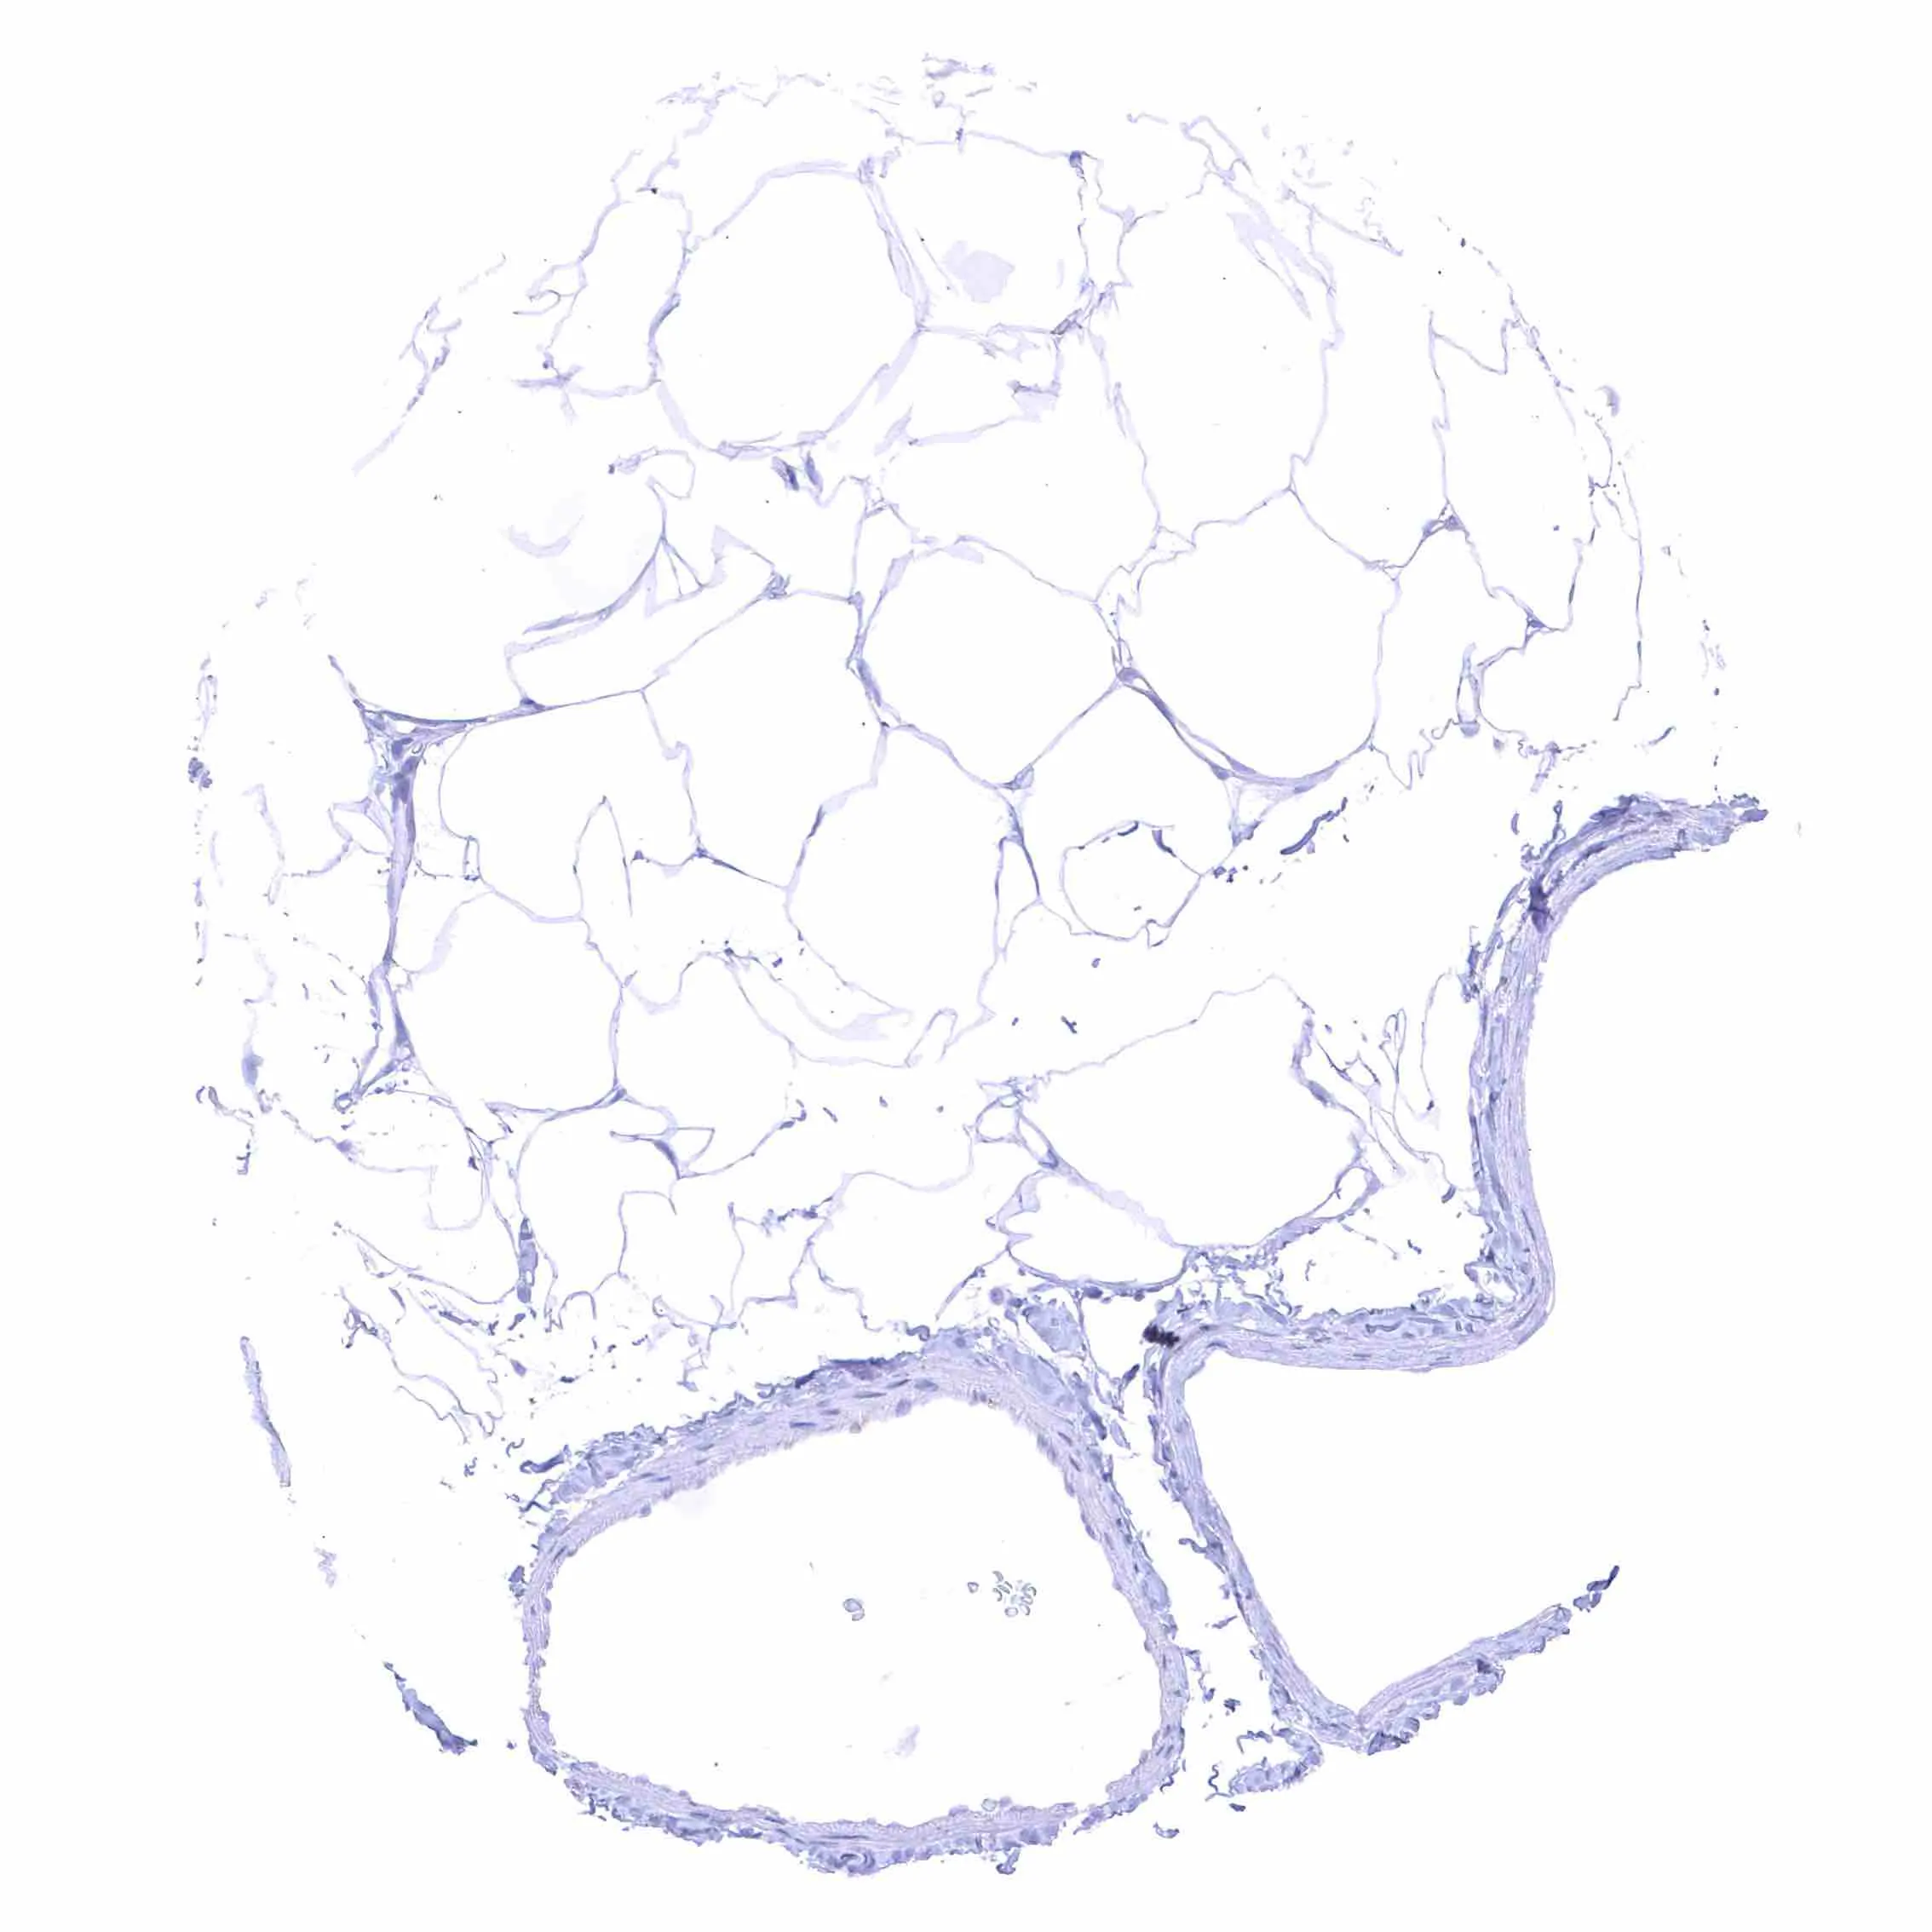

Fat